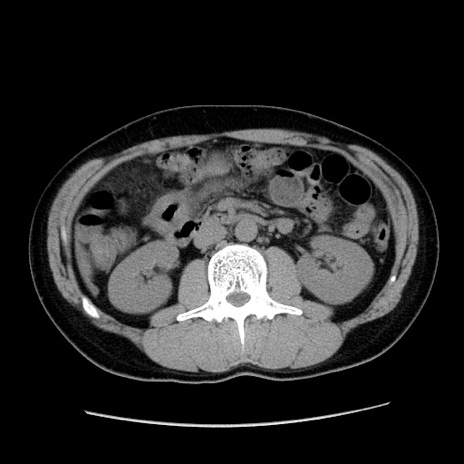

症例36(横断像)

【症例】20歳代 男性

【主訴】心窩部痛

【現病歴】今朝より上腹部痛あり。一旦軽快していたが再度出現したため救急要請。昨日夕に白身の魚を含む刺身を食べた。

【身体所見】BP 136/89mmHg、HR 74/min、BT 37.0℃、腹部:膨満、軟、心窩部に圧痛あり。反跳痛なし、筋性防御なし、腸雑音やや亢進あり。

【データ】WBC 17700、CRP 0.48